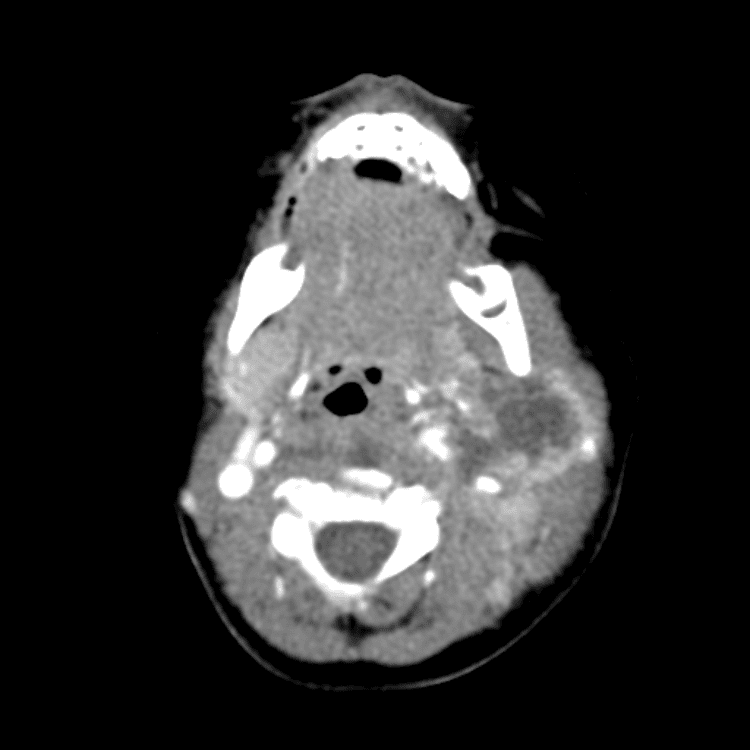

Head and Neck

Simulates call by including subtle or difficult cases and some normals.

27 cases